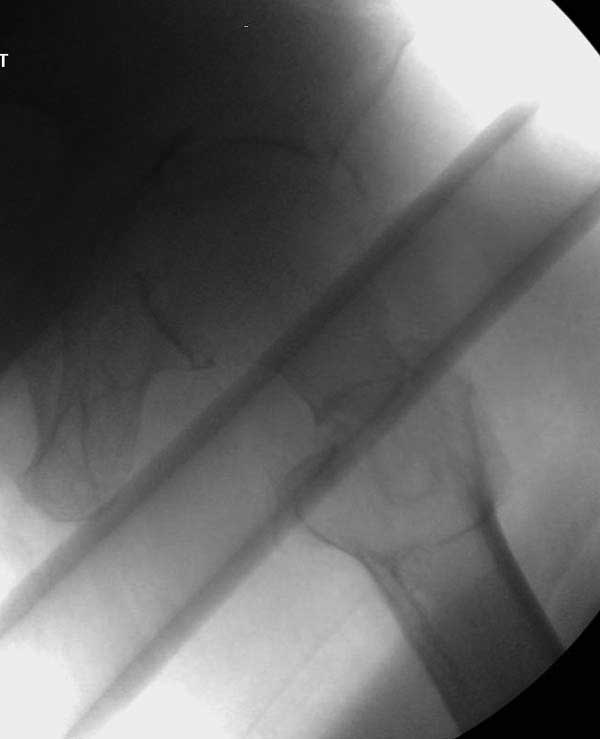

Повторно поступает после двух с половиной лет, где обнаруживается перелом на второй стороне. Немного сложно, но для фиксации выбрали Antegrade InterTan Smith Nephew Nail и с момента фиксации более 3х мес.